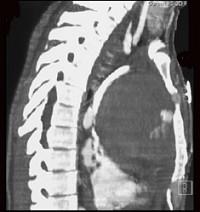

男,33岁,右胸部外伤,胸闷、气短,结合CT图像,最可能的诊断是 ( )A、淋巴管瘤B、淋巴瘤C、纵隔血肿D、畸胎瘤E、胸腺瘤

问题 男,33岁,右胸部外伤,胸闷、气短,结合CT图像,最可能的诊断是 ( )

选项 A、淋巴管瘤 B、淋巴瘤 C、纵隔血肿 D、畸胎瘤 E、胸腺瘤

答案 C